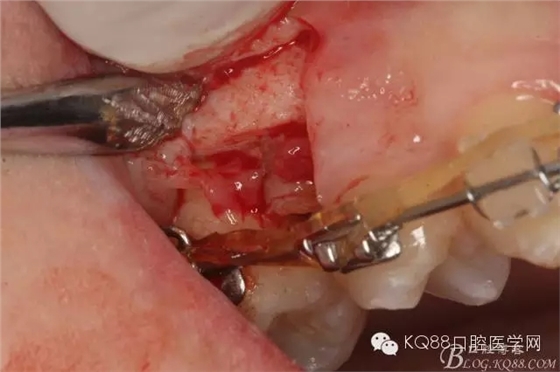

圖8.因16與14合面的間隙僅2mm左右,牙根無(wú)法合向脫位,如何考慮15牙根的脫位將是最大問(wèn)題。高速手機(jī)去除牙間隙內(nèi)的覆蓋在15牙根表面的牙齦組織